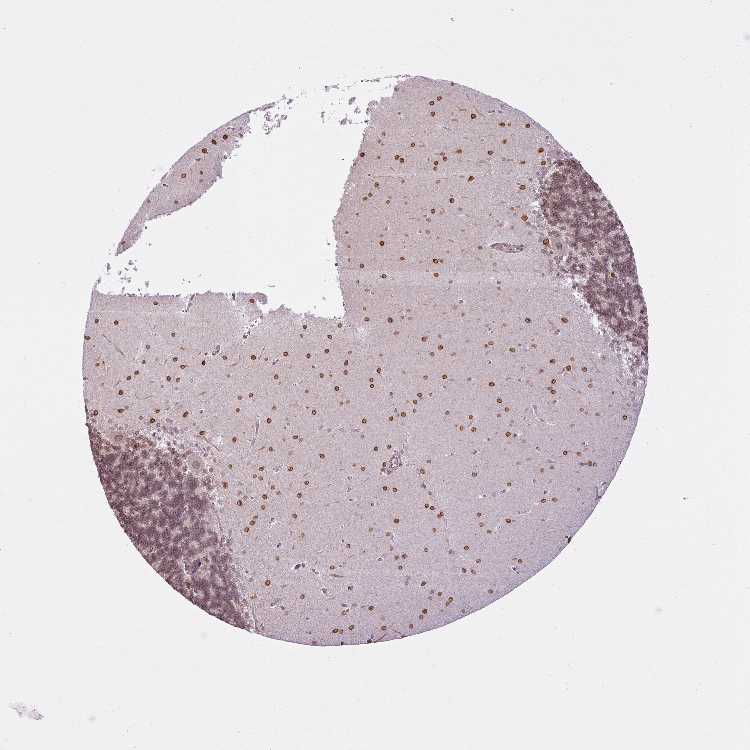

CEREBELLUM - Antibody stainingi

Antibody staining in the annotated cell types in the current human tissue is reported as not detected, low, medium, or high, based on conventional immunohistochemistry profiling in selected tissues. This score is based on the combination of the staining intensity and fraction of stained cells.

Each image is clickable and will lead to virtual microscopy that enables deeper exploration of all samples and also displays staining intensity scores, fraction scores and subcellular localization as well as patient and tissue information for each sample.

Antibody HPA046772Antibody HPA049489

Purkinje cells HighMedium

Cells in granular layer MediumMedium

Cells in molecular layer HighHigh